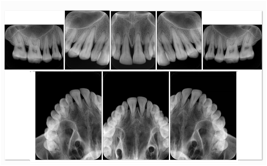

3. A dental provider wishes to capture a series of DICOM IO images for the patient’s dentition. The tooth morphology, teeth are divided into molars, premolars, canines and incisors, and a number of images for each jaw. The anatomic information was captured utilizing the triplet of schema. This standard code sequence is based on ISO 3950-2010, Dentistry - Designation system for teeth and areas of the oral cavity.

Every IO image should have anatomic information either through the primary or modifier sequence.

In most standard cases, images are oriented in structured layouts. These structured displays are useful to be shared between providers for reference purposes.

Table OO.1.1-1 shows structured display standard templates, where Viewset ID is based on the Japanese Society for Oral and Maxillofacial Radiology (JSOMR) classification provided by JIRA (Japan Medical Imaging and Radiological Systems Industries Association, www.jira-net.or.jp). Expected or typical teeth to be imaged location, region and designation codes are based on ISO 3950-2010, Dentistry - Designation system for teeth and areas of the oral cavity. For all the hanging protocols listed in OO.1.1-1, the value to use for Hanging Protocol Creator (0072,0008) is "JSOMR" and the value to use for Hanging Protocol Name (0072,0002) does not include "JSOMR" (e.g., "DL-S001A", not "JSOMR DL-S001A").